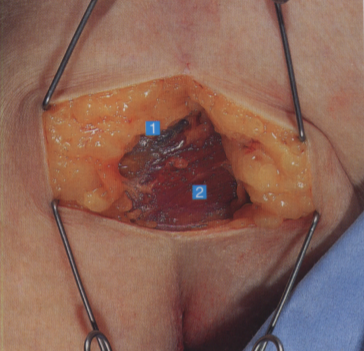

三角肌和胸大肌上的皮下组织,如果仔细观察皮下脂肪边缘,会隐约见到头静脉1. 头静脉;2. 胸大肌

牵开头静脉,可见内侧的胸大肌、外侧的三角肌,以及覆盖肱二头肌短头的筋膜

1. 头静肌;2. 胸大肌;3. 三角肌;

4. 肱二头肌筋膜;5. 肱二头肌短头;

6. 肩胛下肌筋膜;7. 肱骨头;

8. 肩胛下肌和关节囊;9. 肱神经;10. 腋神经